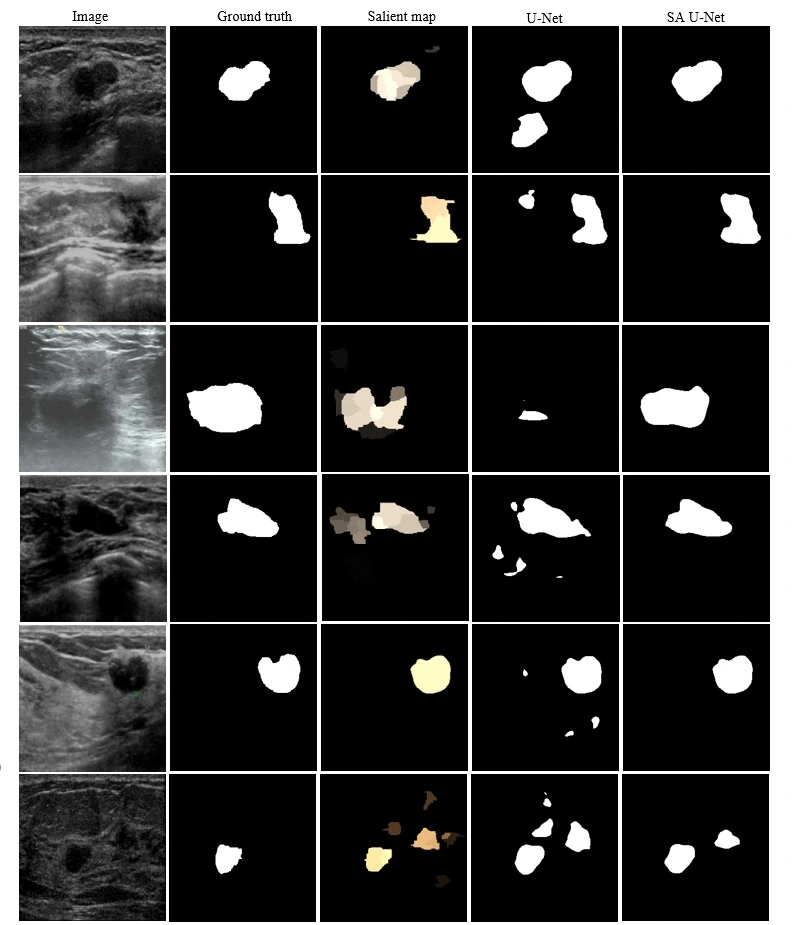

Attention-enhanced U-Net improves breast tumor segmentation in ultrasound by integrating visual saliency to guide feature learning and boost accuracy.